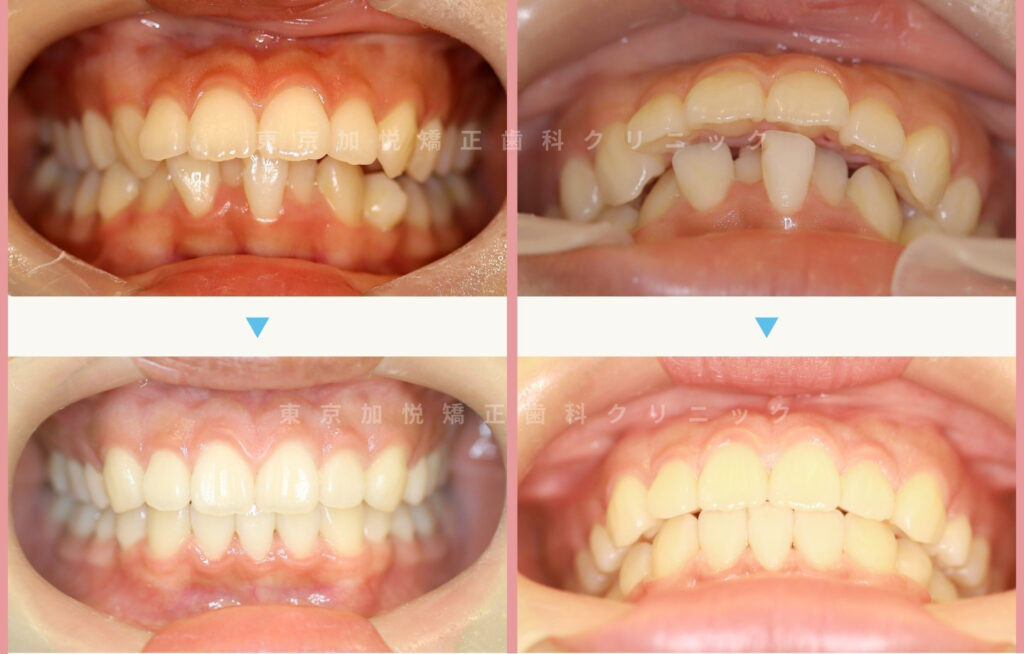

20ヶ月間の矯正で上顎前突がしっかり改善されました

患者様のご希望により、より上顎前突が改善される(治療プラン1)の矯正治療を行いました。

予定通り歯のポジションが整い、しっかり上顎前突が改善されました。

以下は、それぞれの治療前後写真です。

治療後は上下の歯の正中ラインが合っていませんが、より上顎前突の改善が見込める(治療プラン1)を選択したためです。